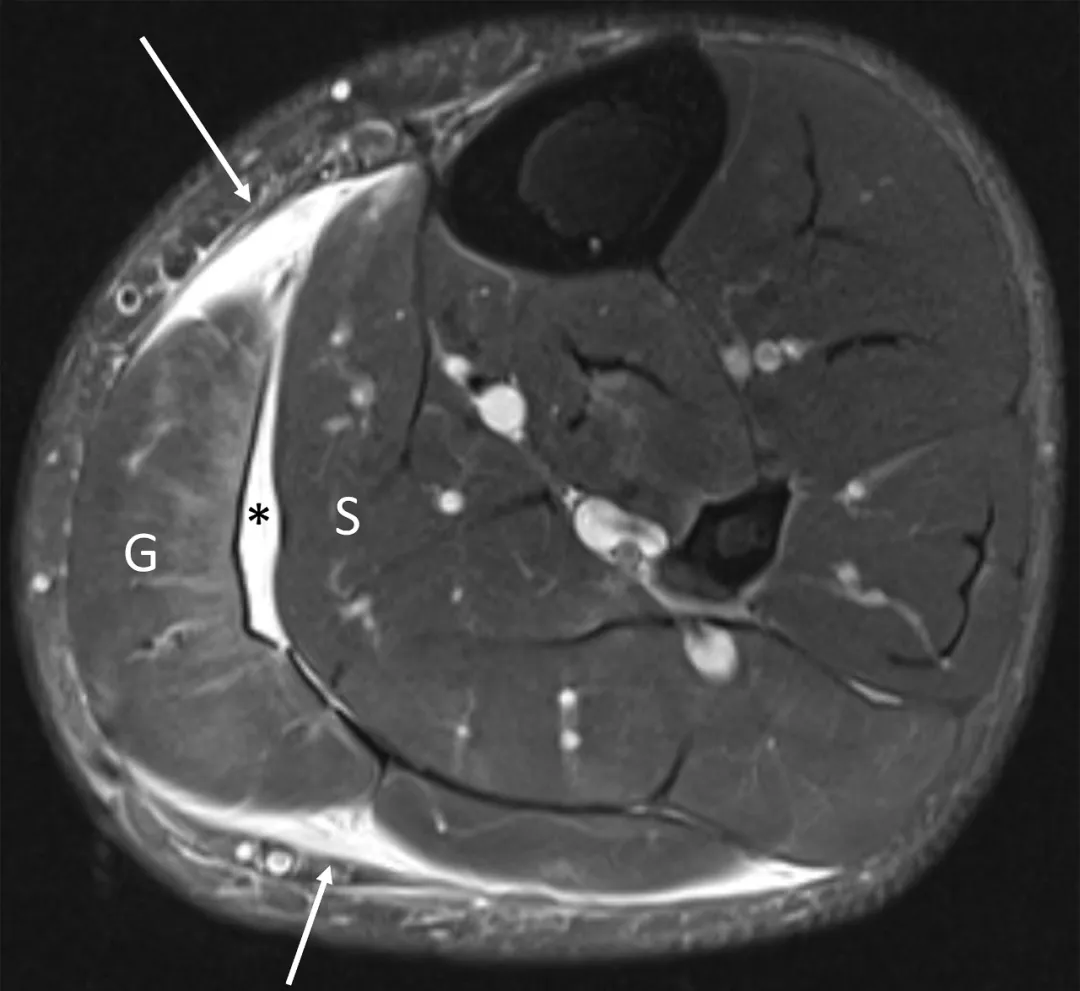

小腿后侧被踢出小腿肌肉挫伤和血肿。横向脂肪抑制T2加权图像显示比目鱼肌和腓肠肌内侧肌腹部沿束的水肿轨迹(箭头)。在两块肌肉之间的筋膜平面形成了血肿(H)。在冠状位T1加权像上,由于内部高铁血红蛋白,亚急性血肿比正常骨骼肌高信号。

高级别腓肠肌劳损。急性小腿疼痛患者的轴向短τ反转恢复(STIR)磁共振图像显示腓肠肌内侧头(G)和比目鱼肌(S)之间的液体(*)追踪。这一发现单独可见于腓肠肌劳损和跖肌腱撕裂。沿肌腱连接处的额外液体(箭头)和腓肠肌内侧头内的水肿表明腓肠肌内侧头重度拉伤伴U形腱膜破裂。这个病例说明了了解小腿肌肉解剖的重要性。